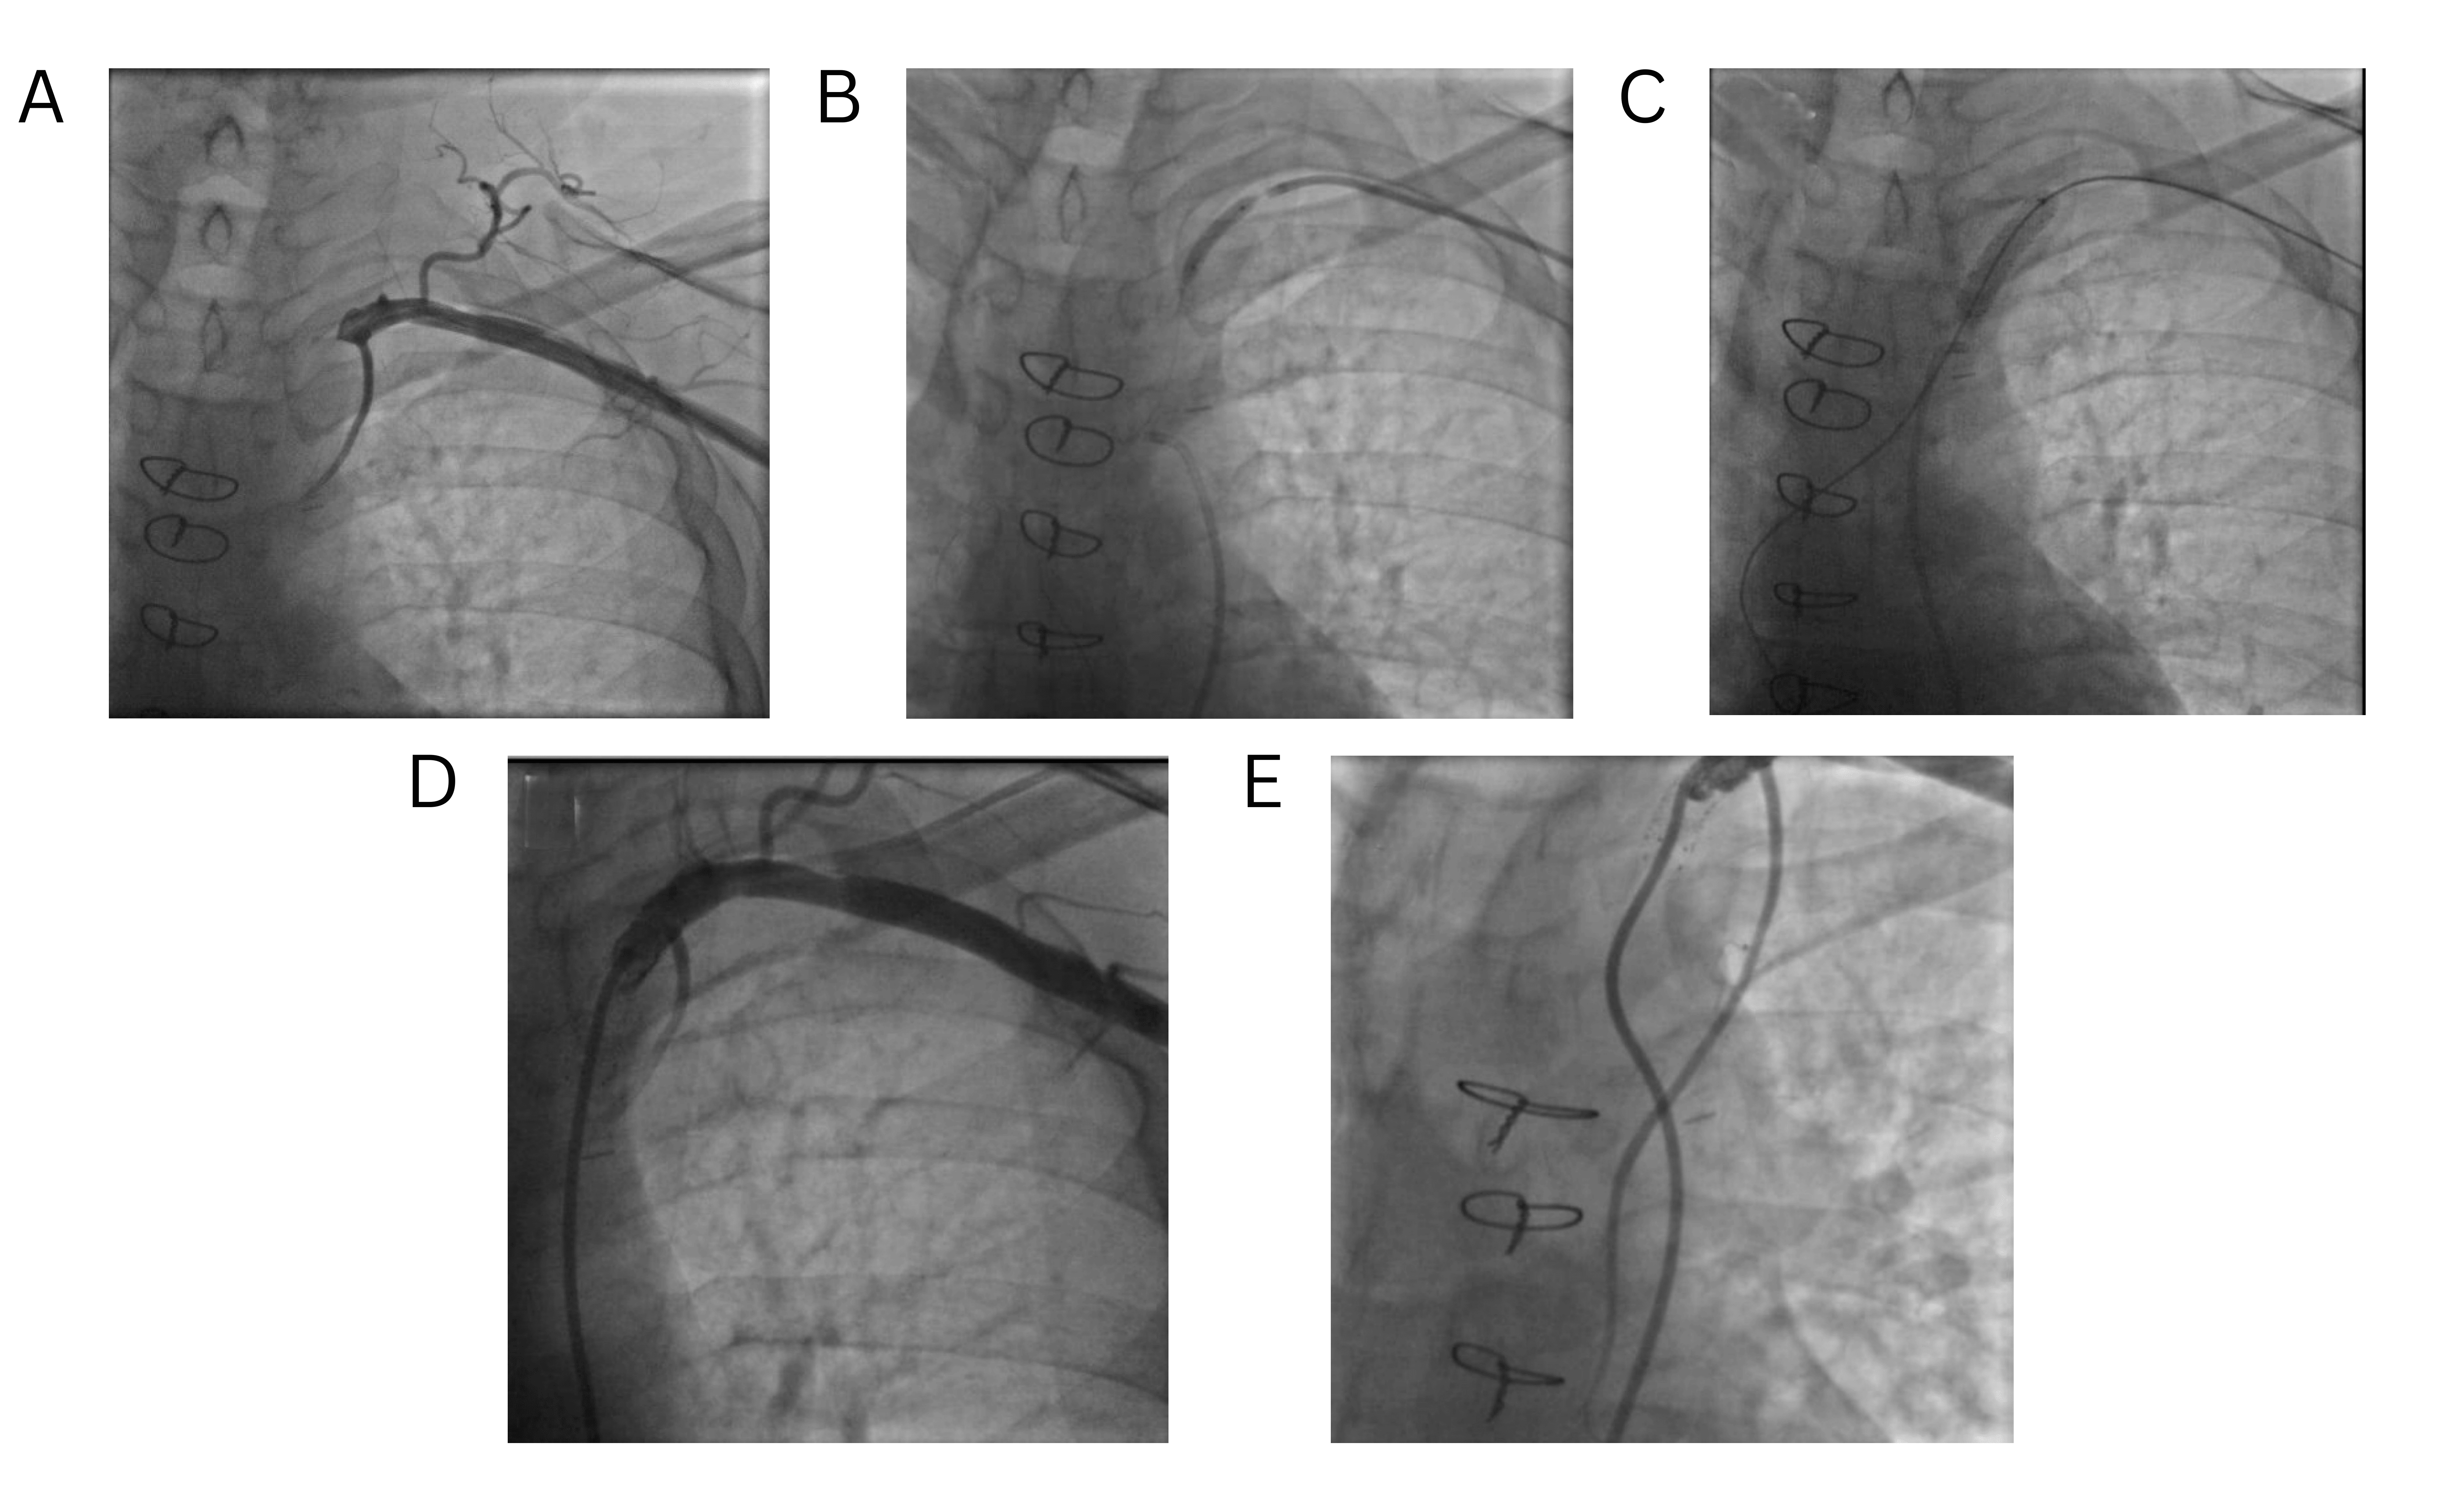

Before thyroxine therapy, in the once-weekly regimen group, the median value of TSH was 9.2 μIU/mL (IQR 6.8 μIU/mL), in the twice-weekly regimen group the level was 9.1 μIU/mL (IQR 7.3 μIU/mL), and in the standard daily dose group the median level was 15.4 (IQR 23.1 μIU/mL). After thyroxine intake and upon follow-up after six months, the TSH level decreased to 4.0 μIU/mL (IQR 3.7 μIU/mL), 4.2 μIU/mL (IQR 5.1 μIU/mL) and 4.5 μIU/mL (IQR 4.9 μIU/mL) in the standard daily, once- and twice-weekly regimen group, respectively (Figure 1) (Table 3). The outcome was statistically insignificant between groups. After six months of follow-up, 56.9% of patients in the daily regimen group, 43.0% in the once-weekly group, and 44.5% in the twice-weekly group achieved TSH levels within the normal reference range (Figure 2).

Compared to the daily treatment group, patients in the once-weekly group had an odds ratio (OR) of 0.659 (95% CI: 0.310–1.398, p = 0.277), and those in the twice-weekly group had an OR of 0.763 (95% CI: 0.363–1.602, p = 0.474), indicating no statistically significant difference in achieving normal TSH between the treatment regimens. Gender was not a significant predictor; males had an OR of 1.845 (95% CI: 0.439–7.751, p =0.403) compared to females. Age and baseline TSH similarly did not significantly influence the likelihood of achieving normal TSH (OR = 0.997, p = 0.801 and OR = 0.995, p = 0.317, respectively) (Table 4).